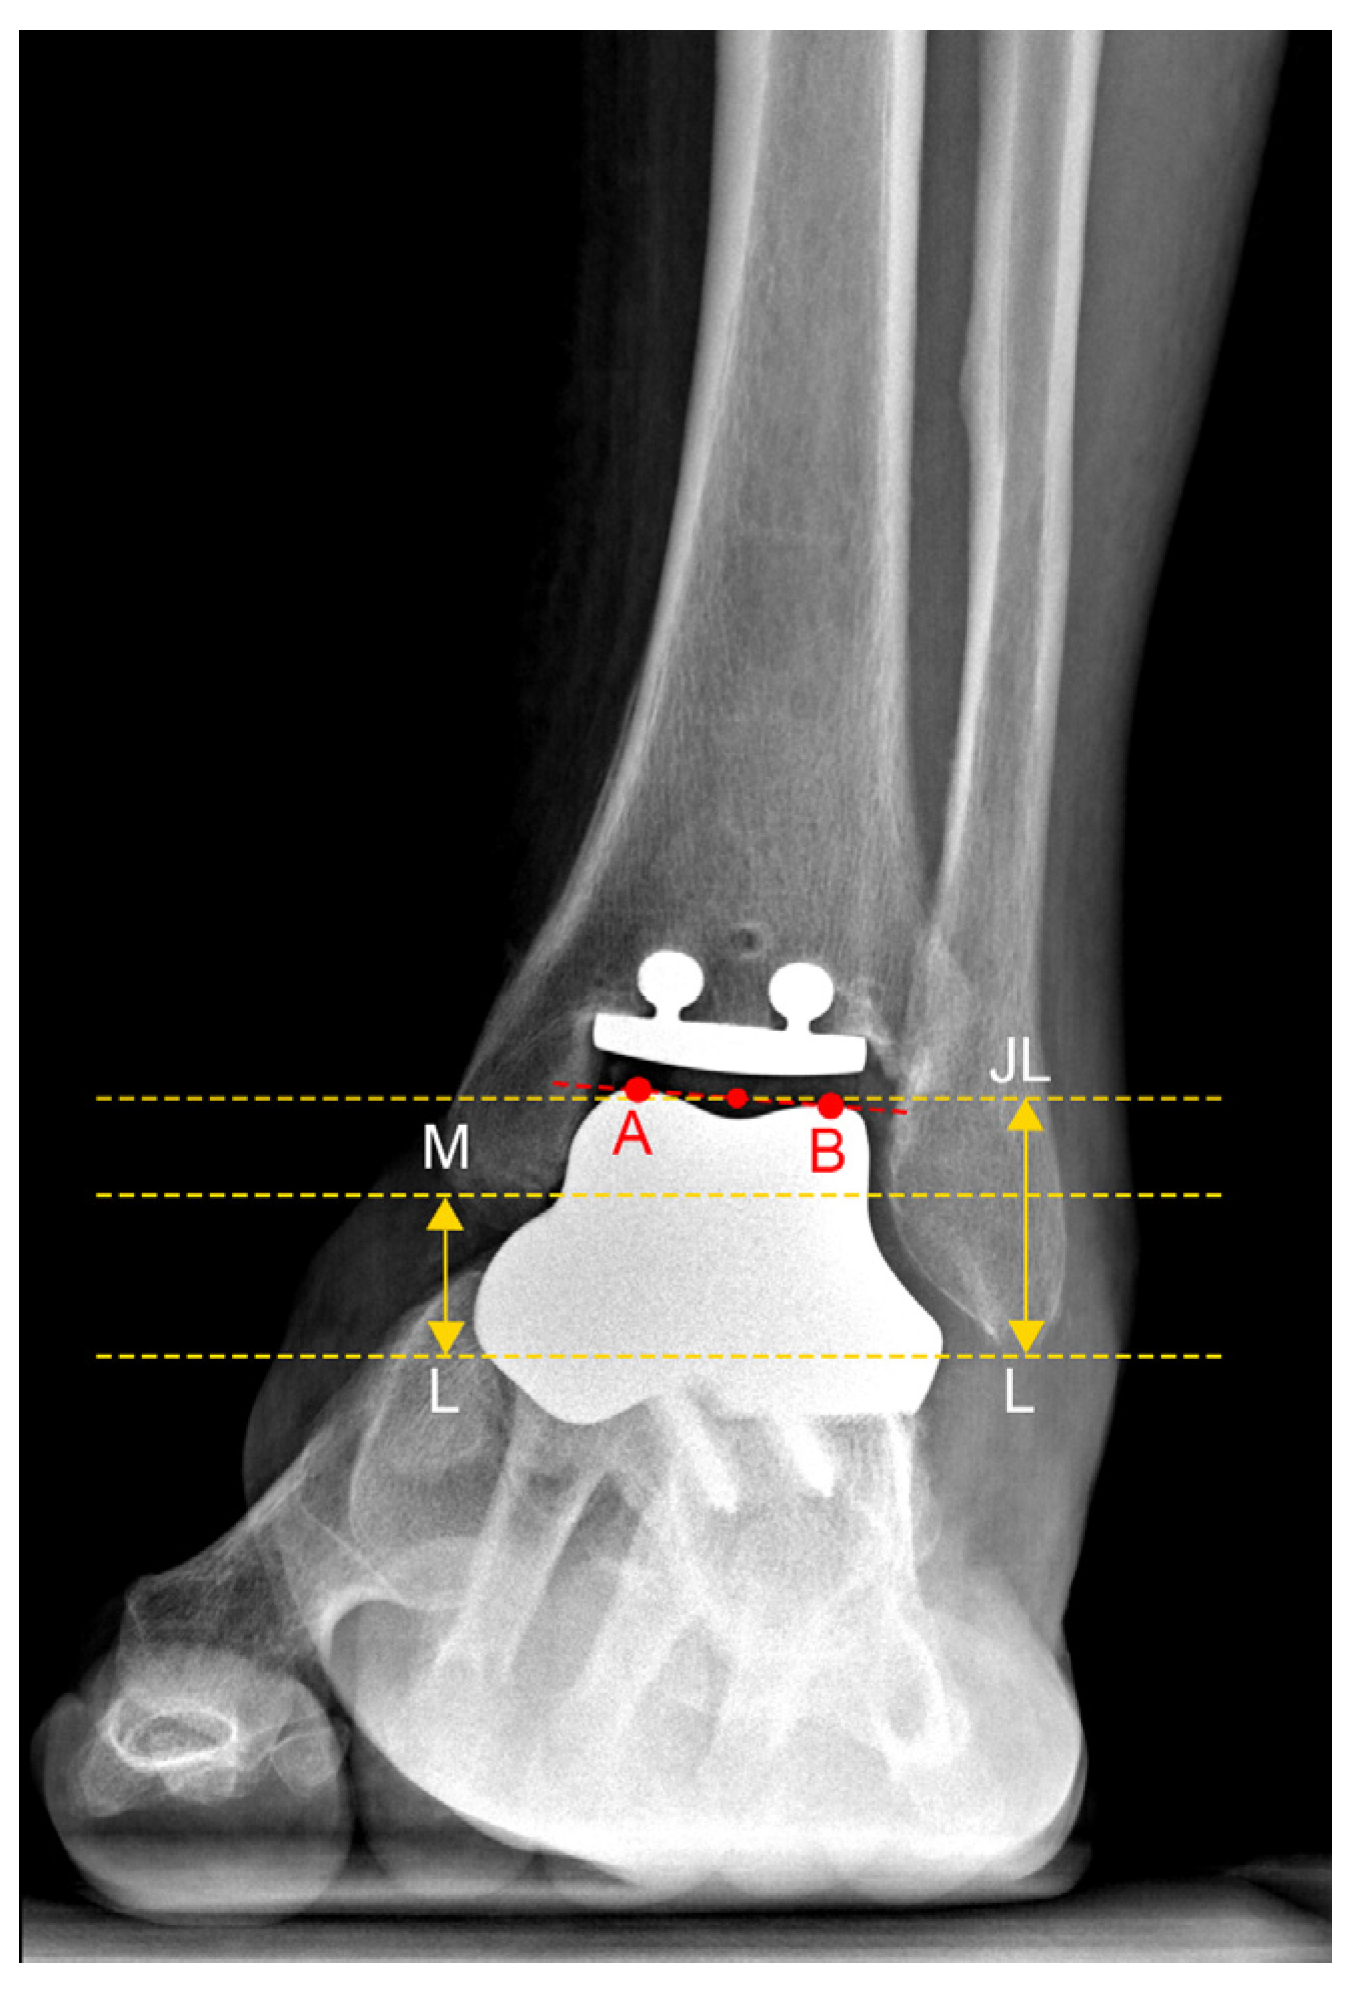

| JLHR 1 | 2.23 ± 0.54 | 1.94 | 1.64–3.44 | 24.3% |

| LM-JL 2 distance | 2.30 ± 0.39 cm | 2.12 cm | 1.78–3.19 cm | 17.0% |

| MM-JL 3 distance | 1.21 ± 0.30 cm | 1.11 cm | 0.89–1.78 cm | 24.9% |

| CS-JL 4 distance | 3.82 ± 0.51 cm | 3.87 cm | 2.94–4.53 cm | 13.4% |

| JLHR 1 (contralateral) | 1.95 ± 0.54 | 1.92 | 1.49–3.54 | 27.7% |

| LM-JL 2 distance (contralateral) | 2.21 ± 0.26 cm | 2.12 cm | 1.84–2.81 cm | 11.8% |

| MM-JL 3 distance (contralateral) | 1.00 ± 0.20 cm | 0.92 cm | 0.76–1.42 cm | 20.3% |

| CS-JL 4 distance (contralateral) | 4.04 ± 0.32 cm | 4.06 cm | 3.46–4.53 cm | 7.8% |